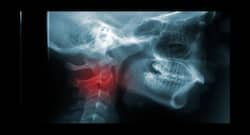

Talking about the symptoms of Head and Neck Cancer, The symptoms includes Red or white patch in the mouth, Persistent sore throat, Frequent nose bleeds and/or unusual nasal discharge.